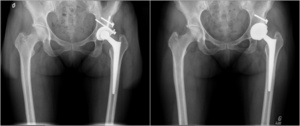

The procedures were performed by five experienced arthroplasty surgeons in our academic institutions. All revision THAs were performed using a posterior approach. The revision was limited to the acetabular component in 26 hips (55%). To retrieve the primary femoral stem, a femoral osteotomy was required in 3 cases (6%). To limit acetabular host bone deficits, the Explant (Zimmer Biomet, Warsaw, Indiana) was used to retrieve the acetabular cup. Allografts were used in 16 cases (34%) to augment acetabular deficits. Press-fit fixation of the acetabular component was obtained by 1 to 2 mm under reaming versus the implant’s outside diameter. Press-fit between the anterior and posterior acetabular rims was achieved in cases where a superior rim deficit was present. One such technique to achieve this was to medialize the implant to increase anterior and posterior rim contact. If superior contact was the preferred option where smaller defects were present; the center of rotation for the hip was elevated by 10 mm. Examples of these principles are demonstrated in Figure 2 and Figure 3.

The mode of fixation of the acetabular implant is widely discussed in the literature. For revision THA, the evidence in the literature suggests cemented fixation has been associated with poor outcomes and a high rate of loosening, whereas excellent outcomes have been documented with press-fit fixation in the revision THA.51–53 Our results also support that in revision THA with limited to moderate bone deficits that do not require structural allograft, adequate press-fit fixation of monobloc acetabular components can be obtained. An adequate press-fit on the anterior and posterior acetabular rims should be sought to optimize fixation. Therefore, if needed, the acetabular component should be medialized before attempting to increase the cup size. In cases of superior bone deficits, a high hip center of up to 10 mm can ensure adequate host bone contact on the superior dome, which is essential for the press-fit stability.54,55 While reaming, surgeons should use increments of 1 mm when approaching the desired diameter to ensure the sphericity of the reamed cavity. If desired, to gain confidence with press-fit only fixation, surgeons could seek adequate fixation with modular components without using screws before switching to press-fit monobloc acetabular components.